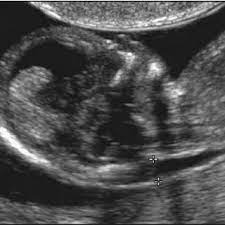

A nuchal translucency scan is part of the ultrasound scan that most pregnant women have at around 12 weeks of pregnancy. When the nt is greater than 3.5 mm, there is a 1 in 5 chance of a chromosome abnormality such as turner or down syndrome, or trisomy 18.additional tests should be ordered by an ob or genetic counselor for confirmation. Heart was strong at 156, and baby was showing me its 10 fingers and 10 toes ️ the elation of seeing my baby quickly flew out the window when the doctor told me the nuchal fold was measuring at 4.5mm which is above the 3mm it should be right now. I'm still waiting for my follow up appointment after my scan results which my gp has said look normal. About one in every 20 women screened will be in this group. I had a normal nt scan of 1.33mm, but had a 1:153 risk ratio for trisomy 21.but my hospital did not give me an overall combined risk ratio with the nt for down syndrome. Some babies with increased fluid don't have down syndrome or any other abnormality. I am 12wks5dys and had my nt scan today. It can be a very scary time but it doesn't mean anything is wrong and the fact that it was 3.6 is good bc that's not that much more than normal. An nt scan is a common screening test that occurs during the first trimester of pregnancy. Also, a negative or normal result (one that shows a decreased risk) does not mean that the baby will not have a chromosome abnormality. It helps doctors determine if a baby is statistically more likely to have a chromosomal abnormality. The nt measure is then analyzed per the gestational age and maternal age to know the risks of abnormality.

The nt scan measures the thickness of the fluid at the back of your baby's neck. I had a normal nt scan of 1.33mm, but had a 1:153 risk ratio for trisomy 21.but my hospital did not give me an overall combined risk ratio with the nt for down syndrome. It is a special ultrasound scan which is performed to specifically measure a tiny bit of fluid that lies under the baby's skin behind the neck known as the nuchal translucency (nt). Between 11 weeks and 13 weeks plus six days of pregnancy or when your baby measures between 45mm and 84mm, crown to rump The nt scan is an ultrasound done in the first trimester to determine your baby's risk of having down syndrome and some other chromosomal abnormalities.

2021 Updated Guide On Ultrasound Nt Scan Timing Results Cost Bookmerilab from bookmerilab.com If you are in this group, you will be offered a diagnostic test. An increased nt measurement does not always mean the baby has a problem but it does increase the risk. This is when they measure the fluid at the back of the baby's neck. A technician will take a quick blood sample from your arm or fingertip. I'm 28 weeks now and baby's heart looks completely normal. I had a normal nt scan of 1.33mm, but had a 1:153 risk ratio for trisomy 21.but my hospital did not give me an overall combined risk ratio with the nt for down syndrome. It is important for the measurement to be done properly to ensure an accurate result. As the nt increases, so does the risk of your baby having chromosomal abnormalities.